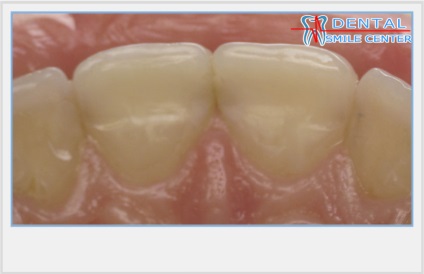

Az alakja a korona, a része az egyes elülső foga, látható, hogy a beteg és az emberek körül, alakított vesztibuláris által határolt felület egy vágóéi, nyak és két érintkező felületek. Anatómiailag a felső elülső fogak vannak elrendezve, mint egy rajongó, így eltérnek a felülről lefelé, hanem a fogazat fogainak koronák a benyomást kelti, hogy közelednek. Ez az illúzió által létrehozott aszimmetria koronák, más néven a jele a korona szög. Klinikailag szerint ez a funkció tetőpontján nyak metszőfogak és szemfogak távközzel helyezkedik el a középső sor a korona laterális, oldalsó metszőfogak több lekerekített sarkok, mint a medialis és a felső könnyezés halmok szemfogak mediálisan elmozdult a központtól a korona. Az ilyen kifejezett aszimmetria a nyak és a vágóél a felső elülső fogak koronák és egyesítjük az aszimmetria az érintkező felületek: valamennyi oldalirányú felületek jobban domború, mind mediális felszínével - közvetlenebb.

A frontális profilja az érintkező felületek az elülső fogak S-alakú, amely egy konvex rész és a konkáv rész.

A domború részét az érintkező felületek szintjén a legnagyobb szélessége a koronát képez két homlokegyenest kapcsolattartó pontok találhatók különböző magasságban. Két szomszédos érintkezési pontja két szomszédos fogak tartalmazhat egy kapcsolattartó pont, amelynek területe egyenlő a kb I mm-elülső fogak.

Klinikailag jelentős átmenetek vannak érintkezési felületek a vestibularis és száj felületén.

Az átmenet az érintkező felületek a vesztibuláris a henger felületét képez kellően hangsúlyos korlátozó reflexió zónában. Ez a zóna korlátozott, kivéve a marginális gerincek, és az egyenlítő a korona és a vágás.